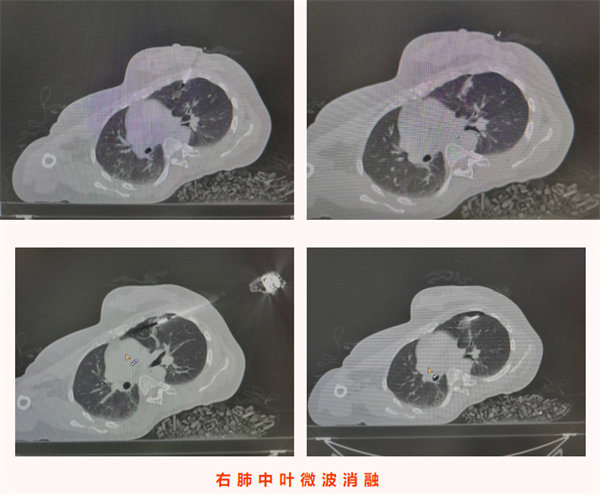

2025年11月24日,王女士的復查影像學檢查顯示:左肺上葉上舌段可見一大小僅0.8cm×0.5cm的微小實性結節,右肺斜裂處可見一0.7cm×0.6cm的實性結節,均為較前新增病灶。結合患者六年前氣管腺樣囊性癌病史,高度懷疑為轉移瘤。由于病灶性質不明且存在轉移可能,王女士為求進一步精準診療來到我院胸心腫瘤外科,門診以“左肺上葉繼發惡性腫瘤”將其收入院。值得注意的是,患者此次就診全程無咳嗽咳痰、發熱寒戰、胸悶氣短等任何典型癥狀,完全是通過規律復查發現的早期病灶,為后續干預贏得了有利時機。

入院后,醫療團隊結合患者既往腺樣囊性癌病史、影像學檢查結果,術前綜合評估后高度懷疑雙側肺結節為腫瘤轉移灶。考慮到患者無明顯癥狀、病灶相對局限,為最大限度減少患者創傷、避免二次手術,團隊決定為其同期實施雙側肺結節診療手術——即CT引導下經皮左肺上葉微小結節穿刺活檢+微波消融術,同期對右肺結節行微波消融術。手術由科主任陳瑜主刀,副主任吳明君擔任助手,魏寶、張寶軍為第二助手。手術過程中,醫師團隊首先聚焦左肺上葉僅0.8cm×0.5cm的微小實性結節,在左側腋下及前外側胸壁精準標記,在患者平靜呼吸狀態下通過CT反復掃描確認穿刺參數,成功獲取活檢組織。并按計劃對左肺穿刺后的結節及右肺斜裂結節同期實施微波消融術,精準破壞雙側病灶組織。整個手術過程一氣呵成,同期完成雙側病灶診療,術中患者生命體征始終平穩。

術后,患者安返病房,生命體征穩定,無胸痛、咯血、氣胸等不適癥狀,飲食睡眠恢復良好。術后病理結果回報,明確左肺上葉結節為腺樣囊性癌轉移灶,與術前評估判斷一致,為后續診療方案制定提供了金標準依據。本例患者無任何癥狀,正是通過定期復查實現轉移病灶的早期發現;同時彰顯了“診斷+治療”一體化微創技術的臨床價值,為惡性腫瘤轉移灶的早期干預提供了高效、精準的診療范式,有力保障了腫瘤患者的長期生存質量。